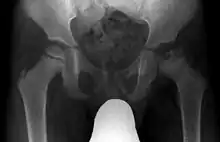

X ray of deformity by Legg–Calvé–Perthes disease of the right hip (left side of X-ray)

Children younger than six have the best prognosis, since they have time for the dead bone to revascularize and remodel, with a good chance that the femoral head will recover and remain spherical after resolution of the disease.[19] Children who have been diagnosed with Perthes' disease after the age of ten are at a very high risk of developing osteoarthritis and coxa magna. When an LCP disease diagnosis occurs after age eight, a better outcome results with surgery rather than nonoperative treatments.[20] Shape of femoral head at the time when Legg-Calvé Perthes disease heals is the most important determinant of risk for degenerative arthritis; hence, the shape of femoral head and congruence of hip are most useful outcome measures.[7]